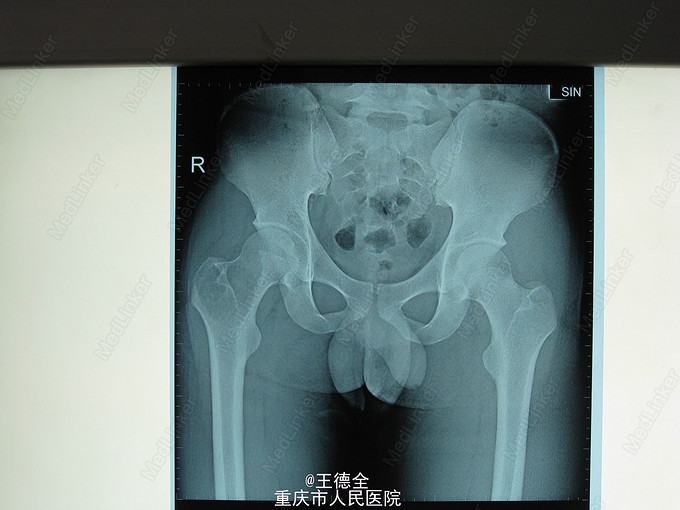

右股骨近端骨巨细胞瘤

患者男,21岁,因右髋部活动时疼痛3周入院,自诉既往无外伤史;查体:右髋部局部压痛,无红肿热痛,右髋关节活动可,右”4“字试验(+),右下肢肌力感觉正常。入院后完善相关检查,积极行病灶清除自体髂骨植骨伽马钉内固定术。